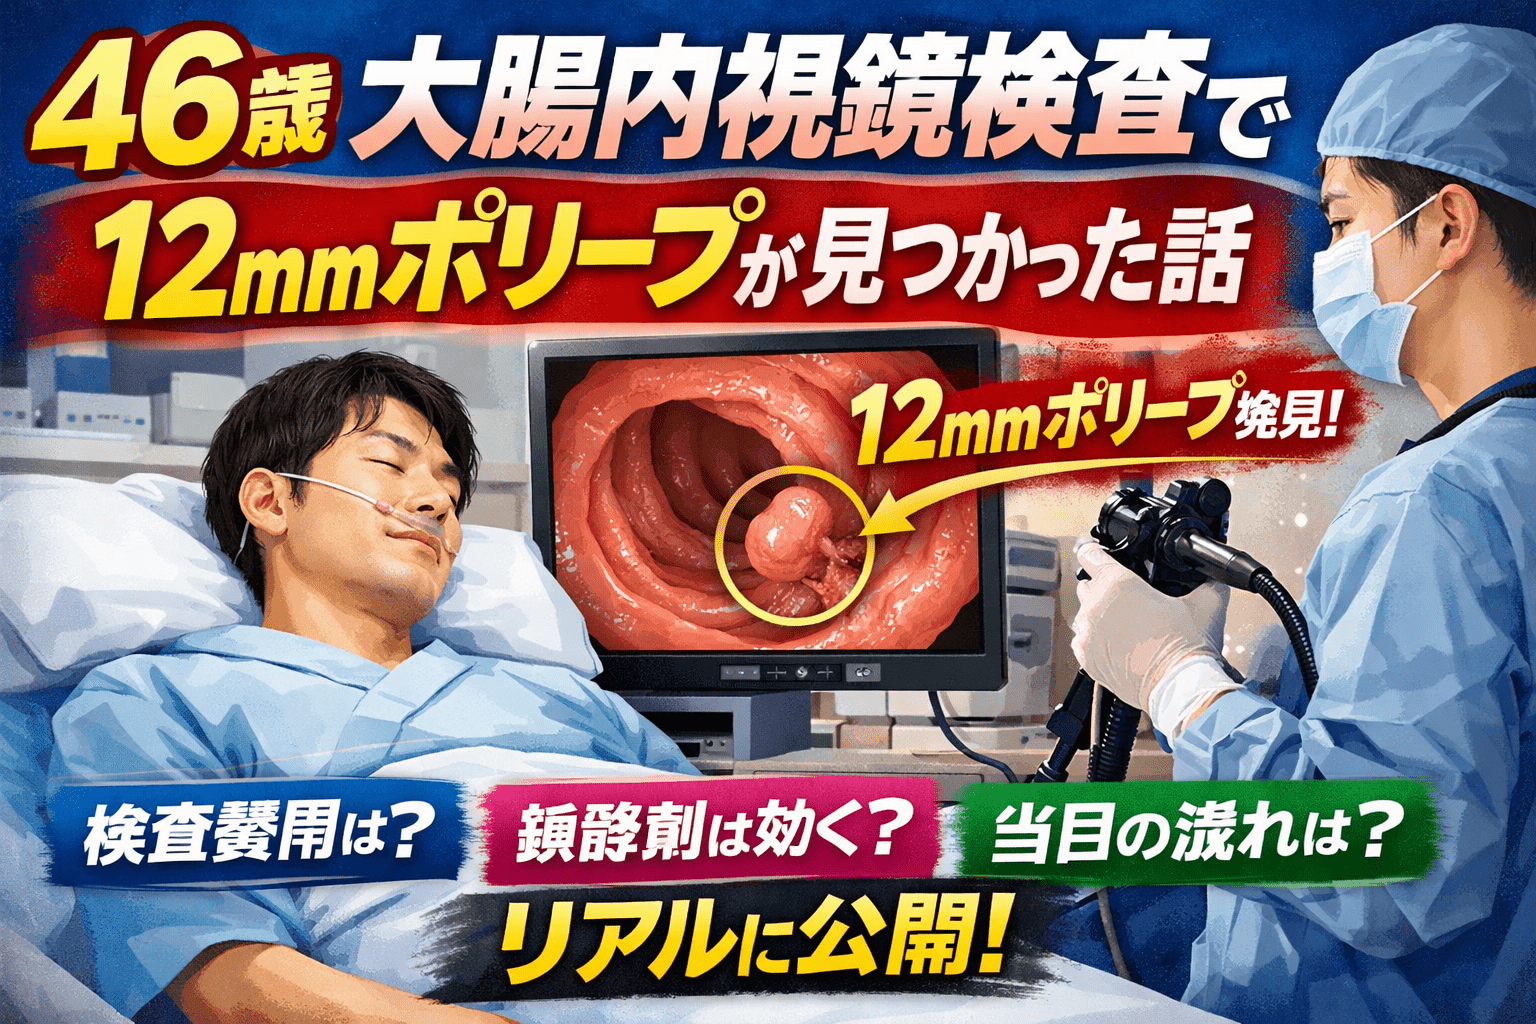

大腸がんは怖い。

それでも46歳になって、一度ちゃんと調べてみようと思った。

結果、12mmのポリープが見つかった。

12mmポリープ発見・その場で切除

検査中にポリープが見つかった。サイズは12mm。

40代に伝えたいこと

便潜血が陰性でも、ポリープはある。

毎年の健康診断で異常なし、自覚症状もなし、それでも12mmのポリープが大腸にあった。

10mm以上のポリープは放置するとがん化リスクが上がると言われている。

早期発見・早期切除できたのは、受けたからだ。

年齢的に一度も受けたことがない人は、今すぐ予約する価値がある。